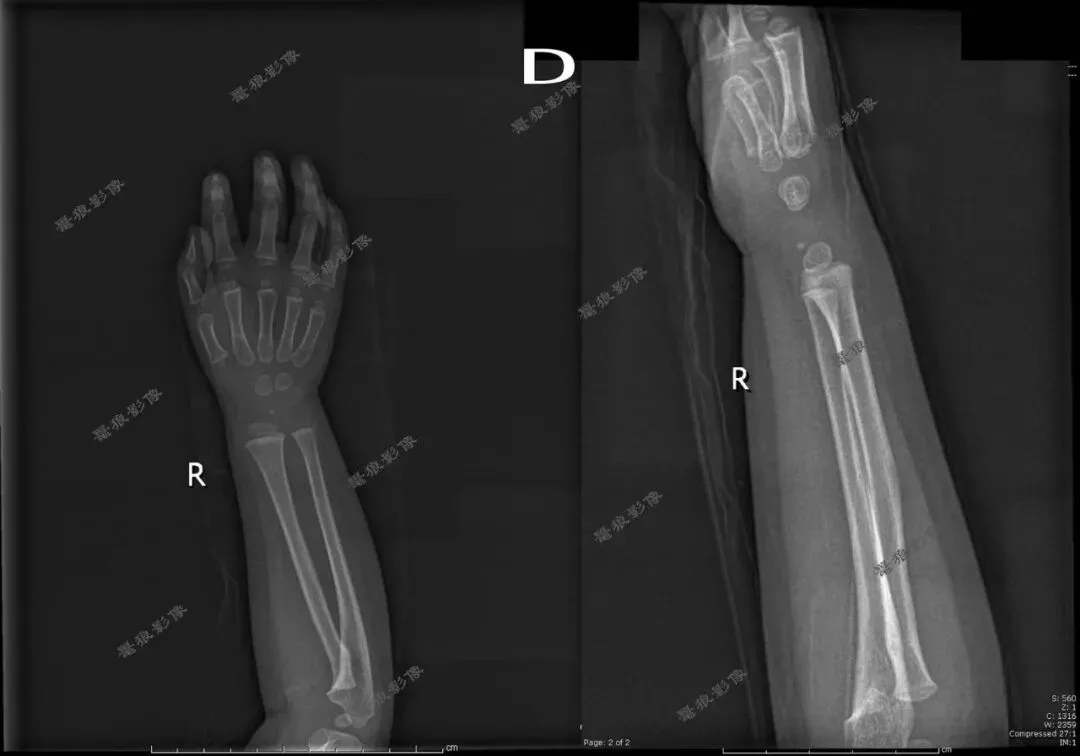

四、桡尺骨正位

2.桡尺骨正位标准影像显示:

(1)显示桡、尺骨正位影像;

(2)腕关节和(或)肘关节呈正位像显示;

(3)诸骨纹理及周围软组织清晰可见。

五、桡尺骨侧位

2.桡尺骨侧位片标准影像显示:

(1)影像显示桡骨、尺骨、腕关节和(或)肘关节侧位影像;

(2)布局合理,图像包括腕关节和(或)肘关节,至少应包括一个关节,桡尺骨呈侧位影像;

(3)清晰显示骨小梁和周围软组织。

三、假如说病人是靠近腕关节那一侧的桡尺骨有问题时,我们拍摄桡尺骨正侧位也只包括一侧腕关节时,这样的拍摄方法(全部伸直或者全部弯曲)也许不会发现此问题。但是病人是肘关节那一侧的桡尺骨有问题时,我们拍摄桡尺骨必须要包括肘关节时,这样的拍摄方法(全部伸直或者全部弯曲)就有问题啦!桡尺骨侧位片伸直显示不出肘关节侧位,桡尺骨正位片弯曲90°显示不出肘关节正位,我们都没法查看肘关节的解剖细节!